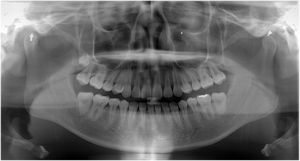

健康な小臼歯を抜いていません

治療前 の レントゲン です 動く矢印治療後 の 歯列レントゲン です